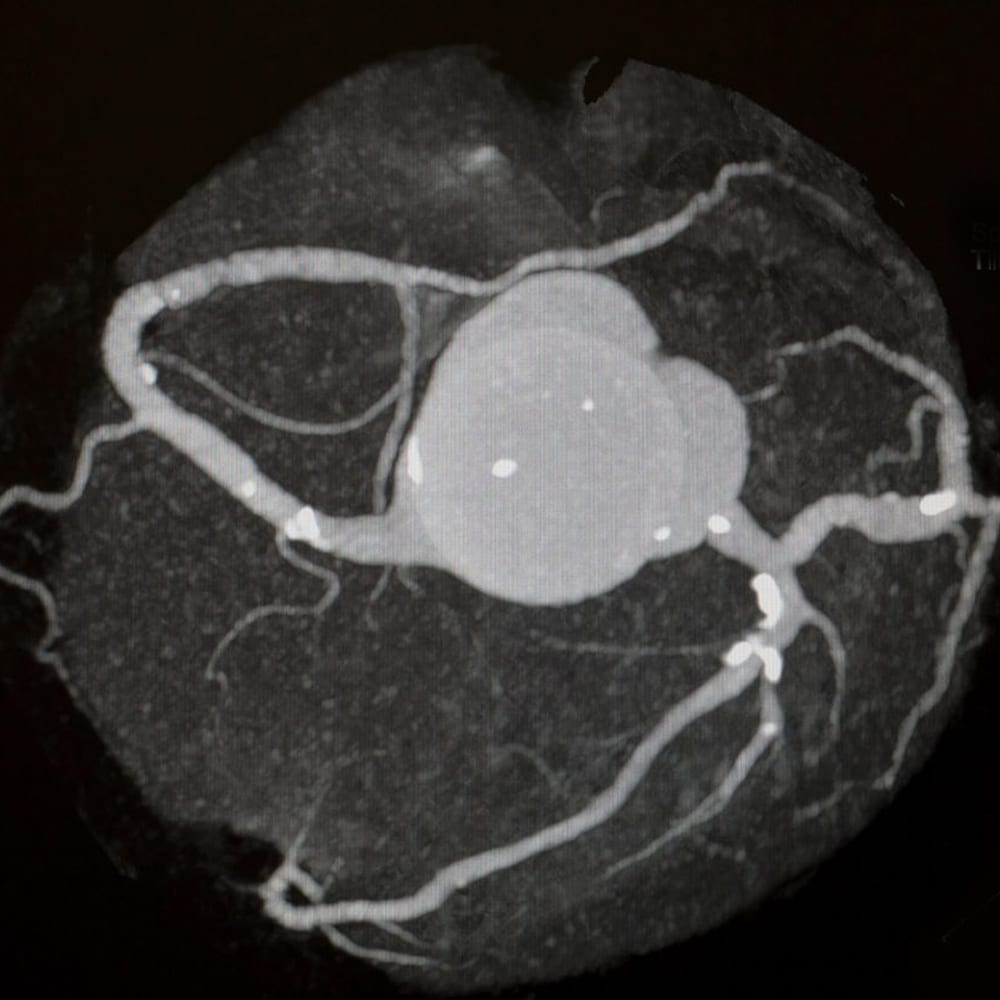

Our Cardiac Calcium Scoring CT is a quick, non-invasive scan that measures the amount of calcified plaque in your coronary arteries. It’s designed as a screening test to help detect coronary artery disease and risk-stratify patients to support treatment plans and measure heart risk. This is a private, self-pay service and is not covered by OHIP.

- Evaluates calcified plaque in the coronary arteries

- Used to screen for coronary artery disease risk

Quantifies Coronary Artery Calcium

Measures calcified plaque in the coronary arteries

Non-Contrast CT Scan

Performed without contrast injection for a safe-quick exam.

Cardiac Calcium Scoring is used as a screening tool to help risk-stratify patients for coronary artery disease. It’s typically considered for people who want a clear understanding of their heart disease risk.

- Measures calcium in the coronary arteries which often cause narrowing of the vessel and heart attacks